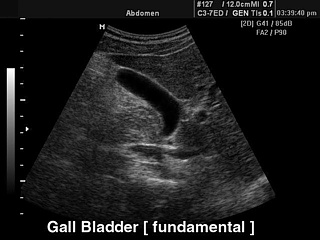

УЗИ желчного пузыря.

Fundamental harmonic (базовая гармоника)